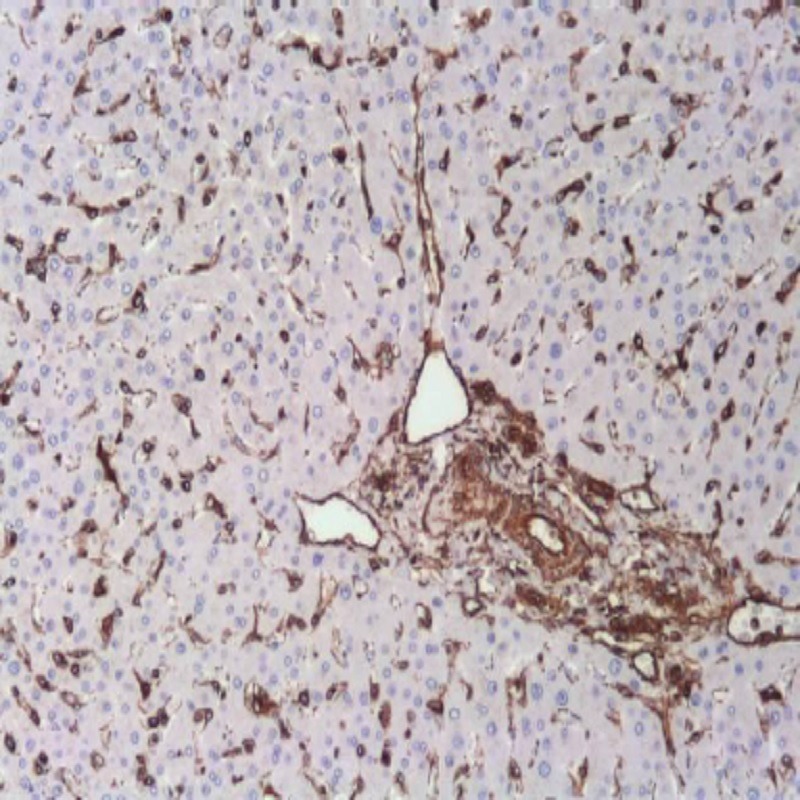

آنتی بادی ویمنتین (Vimentin) برند Novocell یک آنتی بادی مونوکلونال است که می توان از آن در ایمونوهیستوشیمی روی بافت‌های پارافینی استفاده کرد. این آنتی بادی پروتئین ویمنتین را که یکی از اصلی‌ترین پروتئین‌ های فیلامنت‌ های میانی در سلول‌ های مزانشیمی است، به طور اختصاصی شناسایی کرده و الگوی رنگ‌ آمیزی سیتوپلاسمی واضحی ایجاد می‌ کند. از این آنتی بادی به عنوان یک نشانگر کلیدی در پاتولوژی تشخیصی برای تایید منشا مزانشیمی ضایعات و کمک به تشخیص سارکوم‌ ها استفاده می‌ شود.

این آنتی بایی به طور گسترده در پاتولوژی تشخیصی به عنوان یک نشانگر مزانشیمی کلیدی مورد استفاده قرار می‌گیرد. کاربرد اصلی آن در تمایز سارکوم‌ها (مثبت برای ویمنتین) از کارسینوم‌ها (معمولا منفی برای ویمنتین) و همچنین کمک به تشخیص تومورهای مزانشیمی خاص مانند لیومیوسارکوم، فیبروسارکوم و آنژیوسارکوم است. همچنین در شناسایی متاستازهای کارسینوم‌ها که دچار تغییرات اپی تلیال-مزانشیمی (EMT) شده‌اند و در مطالعات مربوط به فیبروز بافتی نیز کاربرد دارد.

The Novocell Vimentin antibody (Clone SP20) serves as an essential mesenchymal marker in diagnostic pathology, particularly for confirming sarcomas and detecting epithelial-mesenchymal transition.